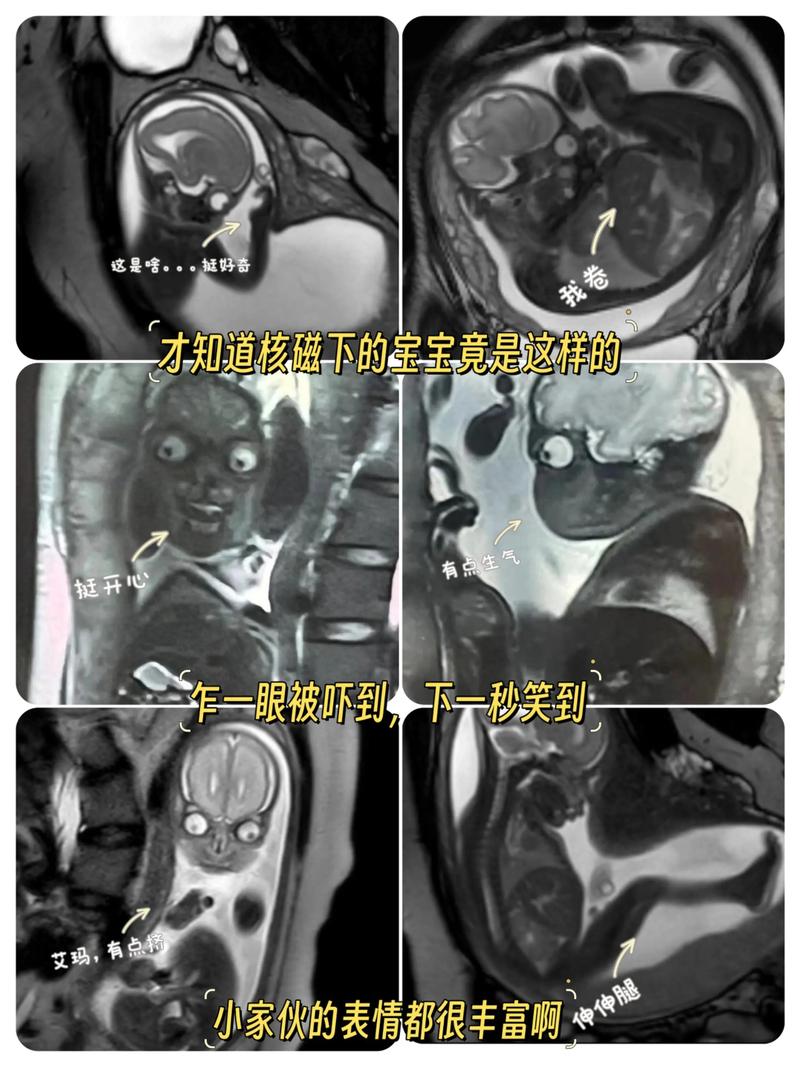

新生儿核磁共振(MRI)到底查什么?新手爸妈必读的权威指南

每一个新生命的降临都伴随着无尽的喜悦与期盼,有时在产检或新生儿期,医生可能会提及一个让家长心头一紧的词——“核磁共振”(MRI),特别是对于刚出生的宝宝,这个“庞然大物”似乎充满了未知与恐惧。

您的担忧,我们感同身受,作为医生,我的首要任务不仅是诊断疾病,更是为您和您的家庭提供清晰、安心的信息,本文将彻底解答您的所有疑问,让您明白,新生儿核磁共振并非洪水猛兽,而是一位能精准“侦察”宝宝身体内部情况的“超级英雄”。

- 原理: 利用强大的磁场、无线电波和计算机技术,生成人体内部精细的、多维度的图像,它就像一个“超级声波”,但完全没有辐射。